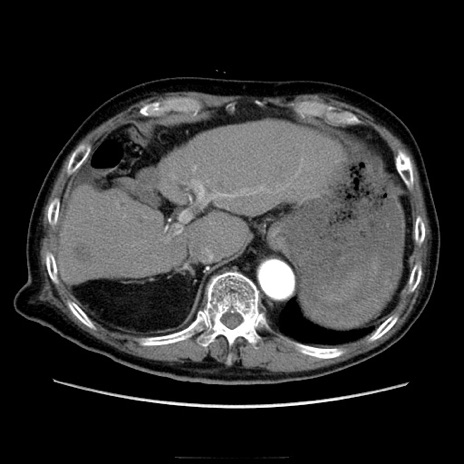

症例21(横断像)

【症例】70歳代男性

【主訴】腹痛

【現病歴】肝硬変・肝細胞癌にてかかりつけの方。約9時間前に食後より腹痛出現。症状が徐々に増悪し、嘔吐出現したため来院。

【既往歴】肝硬変、肝細胞癌(RFA、TACE後)

【身体所見】意識清明、表情苦悶様、BT 36℃、BP 129/78mmHg、P 88bpm、SpO2 97%(RA)、右上腹部から心窩部にかけて圧痛あり、反跳痛なし、筋性防御あり。

【データ】WBC 5800、CRP 0.16